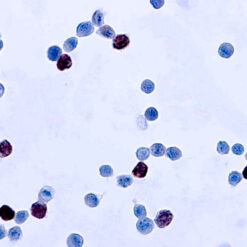

Cytokeratin (CAM5.2)

Anti-Cytokeratin (CAM 5.2) reagent has a primary reactivity with human keratin proteins that correspond to Moll’s peptides #7 and #8, Mr 48 and 52 kilodaltons (kd), respectively. Cytokeratin 7 and 8 are present on secretory epithelia of normal human tissue but not onstratified squamous epithelium. Anti-Cytokeratin (CAM 5.2) stains most epithelial-derived tissue, including liver, renal tubular epithelium, and hepatocellular and renal cell carcinomas. Anti-Cytokeratin (CAM 5.2) might not react with some squamous cell carcinomas.

| Positive Control Tissue | Colon, Lung, prostate and breast tissue. |